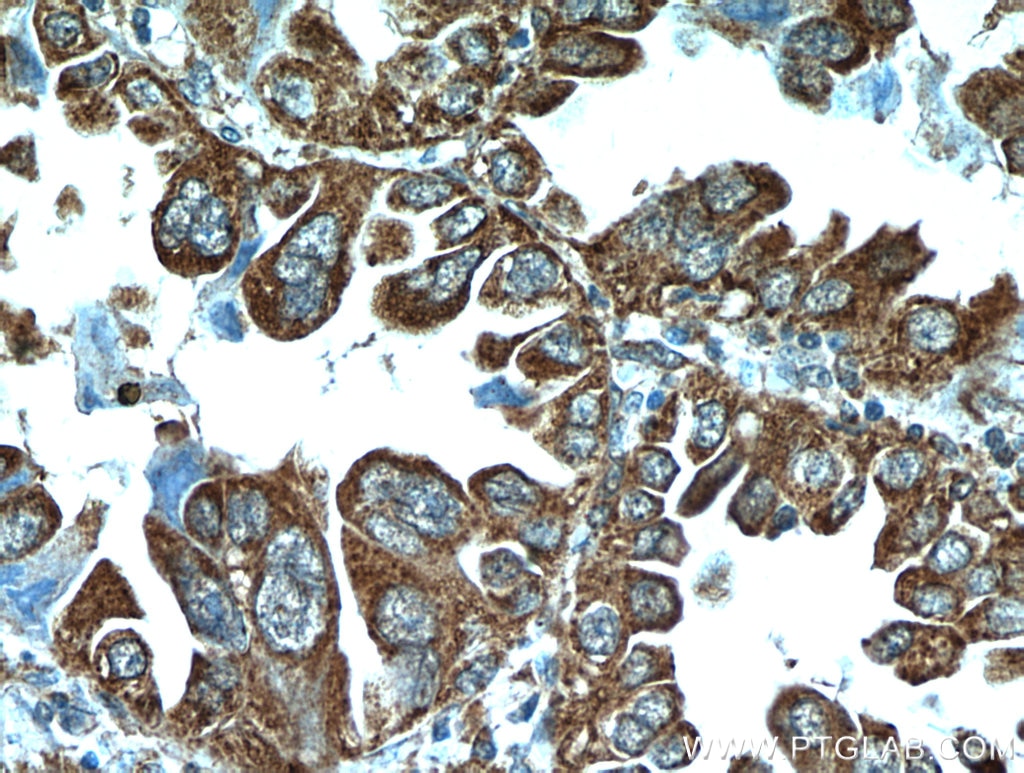

| Positive IHC detected in | human lung cancer tissue Note: suggested antigen retrieval with TE buffer pH 9.0; (*) Alternatively, antigen retrieval may be performed with citrate buffer pH 6.0 |

| Immunohistochemistry (IHC) | IHC : 1:20-1:200 |